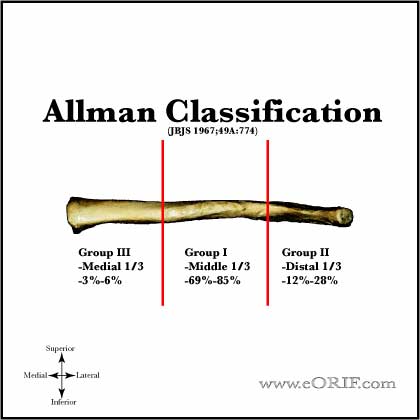

What type of fracture is a clavicle fracture?

Clavicle fractures are classified into three types based on the location of the fracture: 1) near the sternum (least common), 2) near the AC joint (second most common), or 3) in the middle of the bone between the sternum and AC joint (most common).